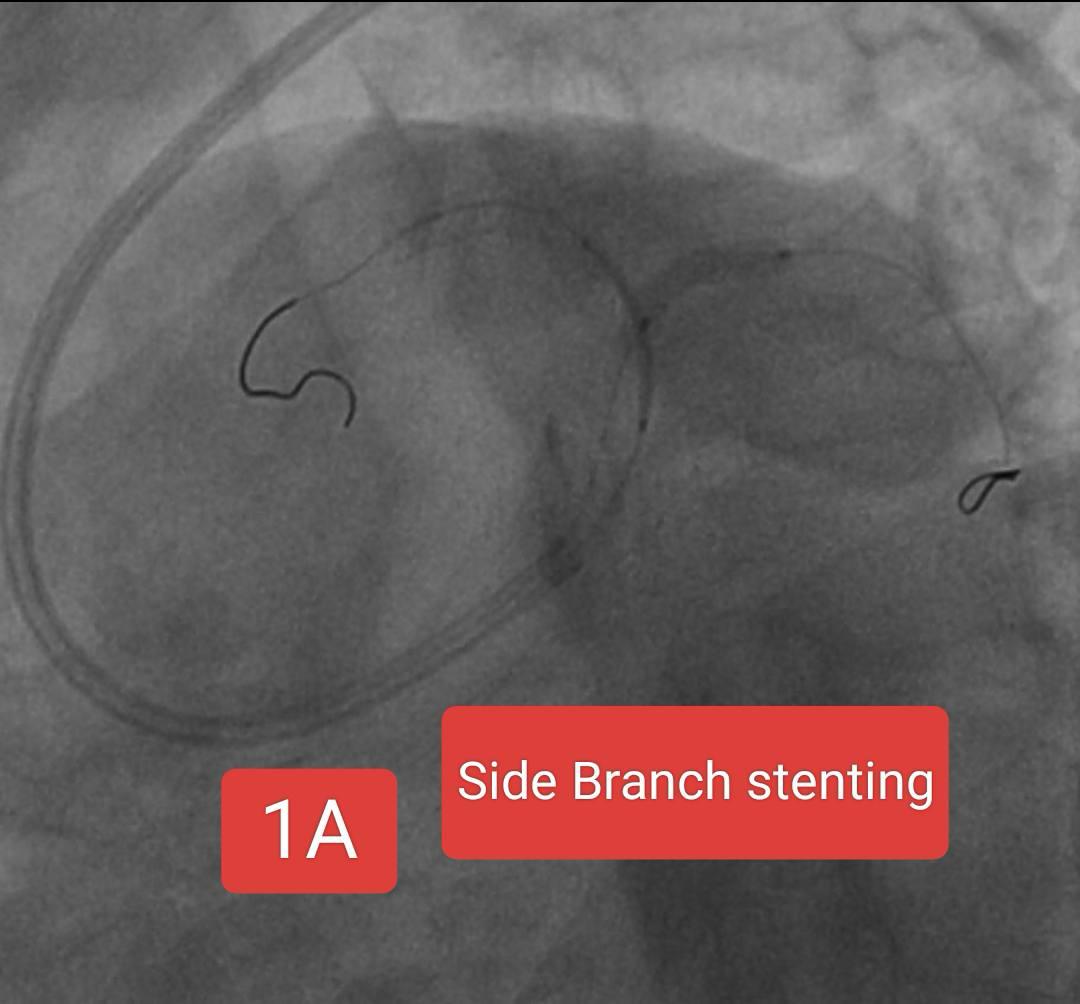

Two interesting cases of Left main stenting by mini crush technique done at Sunshine Hospital ,Bhubaneswar last month. Case 1 A 65 Years old Male Risk factors : Smoking, Hypertension Presented with Chest pain since 2 days ECG : Anterior wall STEMI ECHO : RWMA LAD Territory, LVEF 38% CAG : Left main + LAD + LCx disease PTCA done : Left main bifurcation stenting by Mini crush technique Case 1B 72 year old Male Risk factor : Smoking CAD Post PTCA status to OSTIOPROXIMAL LAD - D1 ( Bifurcation) ( 2020) Medications discontinued since 2022. ECG : aVR ST elevation ECHO : RWMA LAD Territory, LVEF : 45% CAG : Distal LMCA 95%, ostial LAD stent ISR 95% , ostial LCx 99% Patient refused CABG PTCA done : Left main bifurcation stenting by Mini crush technique Thanks to our cath lab team ( Sarfaraj Ahammed , Amit Gourav Bagh , Madhu Smita Swain , Anjan Jagannath Dash, Sanjib, Mami didi, Sameer and Raju) and Sunshine Hospital Bhubaneswar